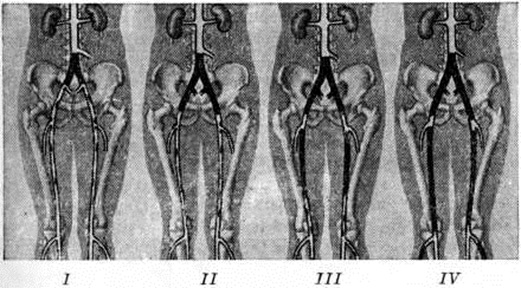

Топическую картину поражения можно установить пробой изотопной и рентгеноконтрастной ангиографии. Изотопная ангиография (смотри полный свод знаний) осуществляется пробой внутривенного введения технеция 99-м. Из методов рентгеноконтрастного исследования предпочтение следует отдать транслюмбальной пункционной аортографии (смотри полный свод знаний), при которой возможно получить изображение не только аорты, но и дистального сосудистого русла конечностей. Именно аортография выявляет локализацию и протяжённость поражения (рисунок 4—6), однако её следует проводить только при решении вопроса об оперативном лечении больного.

Рис. 5.

Аортограмма (прямая проекция) больного с синдромом Лериша при неспецифическом аортоартериите: резкое сужение инфраренального сегмента аорты (указано стрелками), поражение висцеральных ветвей.

Рис. 6.

Аортограмма (боковая проекция) больного с синдромом Лериша при высокой окклюзии аорты: 1 — резко расширенная аорта; 2 — пункционная игла для введения контрастного вещества.